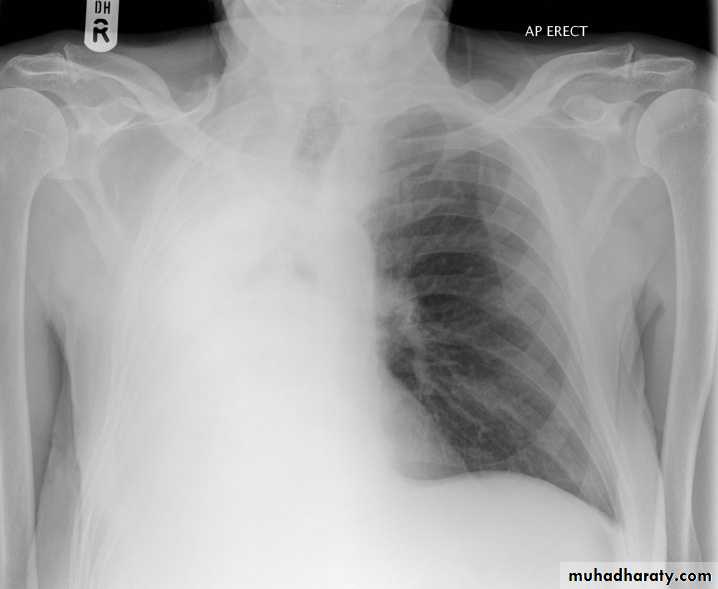

The main aims of investigations are to confirm the diagnosis, establish the histological cell type and define the extent of the disease.1-CXR: common radiological features of bronchial carcinoma;

Unilateral hilar enlargement.

Peripheral pulmonary opacity.

Lung, lobe or segmental collapse.

Pleural effusion.

Broadening of mediastinum, enlarged cardiac shadow, elevation of a hemidiaphragm.

Rib destruction.